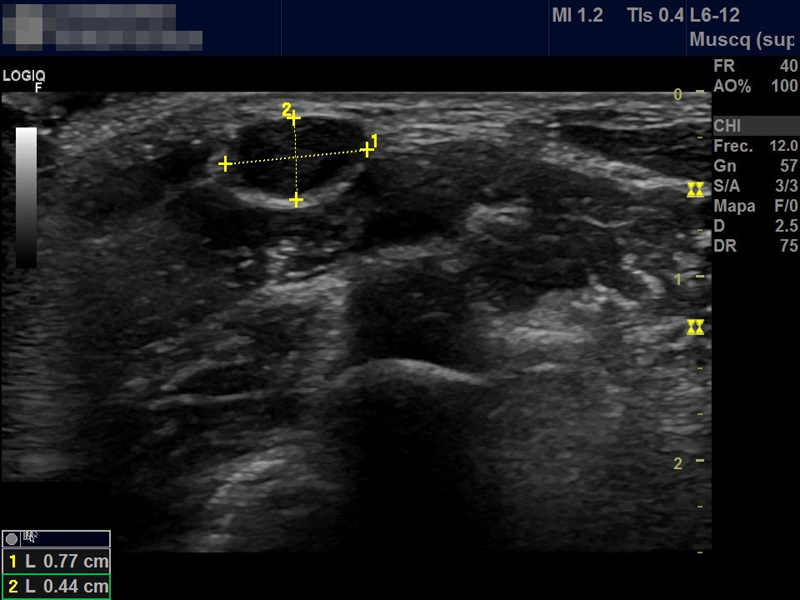

¿Qué es e­sa tu­mo­ra­ción en el cue­llo? U­se­mos la e­co­gra­fía pa­ra sa­ber­lo

Niño de 7 años que acude a consulta de Atención Primaria por aparición de tumoración cervical de 2 días de evolución. A la exploración en la región lateral cervical posterior al esternocleidomastoideo se aprecia una tumoración móvil no adherida de consistencia blanda de aproximadamente 1 cm de diámetro sin cambios superficiales acompañantes.